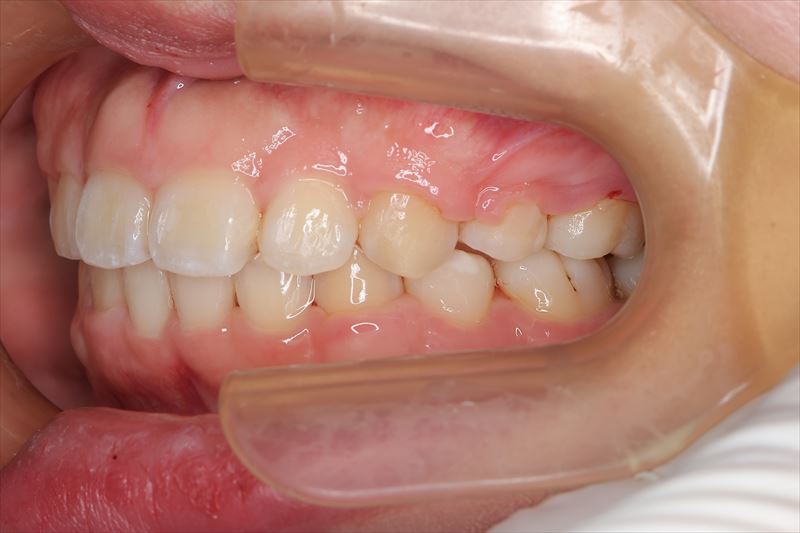

治療前

- 症状

- 叢生、口唇の突出

- 上顎両側4番、下顎右側5番、下顎左側4番抜歯

- 口唇の突出を気にされて来院いたしました。Eラインより口唇の突出、オトガイ部の緊張を認めました。アンカースクリューを用いて前歯の牽引を行うことによって良好な側貌となりました。治療途中で遠方に引っ越されたため来院が困難となり治療期間が延びてしまいましたが、患者様のご協力もあり無事に治療を終えることができました。